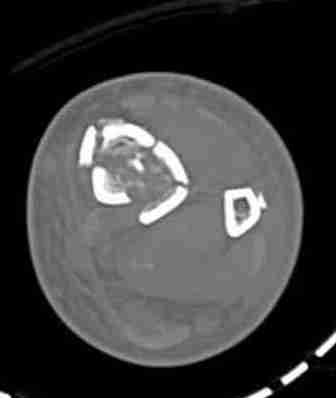

КТ пилона имеем.

Предыдущей сменой до 4:00 утра по поводу открытого перелома бедра, тибиал плато, пилон и надколенника сделана операция.

Пострадавшему 21 г., травма скоростная, после I&D с расширением раны, на бедре сделана операция ретроградным интрамедуллярным штифтом, остеосинтез с частичной резекцией надколенника и ушивание собственной связки.